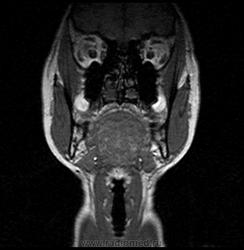

06.06.2011 МРТ - головы и шеи.

Пацентка 36 лет, с жалобами на припухлось в околоушной области справа.

В глубокой доле  правой околоушной железы  на фоне неизмененной паренхимы зона  гетерогенного по Т2, гипоинтенсивного по Т1  с единичными гиперинтенсивными включениями.При контрастировании- накопление контраста диффузное неоднородное и по периферии.Рискну предположить злокачественное образование ( аденокарцинома) с низкой степенью злокачественности( есть капсула, экспансивный рост).Сильно не расстреливайте.

Проблема в том, что перед челюстно-лицевым хирургом стоит распространенность любого объемного процесса, в данном случае все упирается в возмможную травму лицевого нерва и конечно же с дальнейшим его парезом, а ведь женщина  еще молодая. Образование имеет тонкостенную оболочку, по структуре неоднородно, с наличием кальцината, при этом МР-сигнал от окружающих анатомических структур(как костных так и мышечных) не изменен, т.е. об инфильтративном росте речи не идет, в какой то степени доброкачественное. В конкретном случае лицевой нерв с ретромандибулярной веной просто несколько оттеснен.

По гистологии аденома околоушной слюнной железы, но после удаления пока сохраняется парез лицевой мускулатуры, возможно временный.